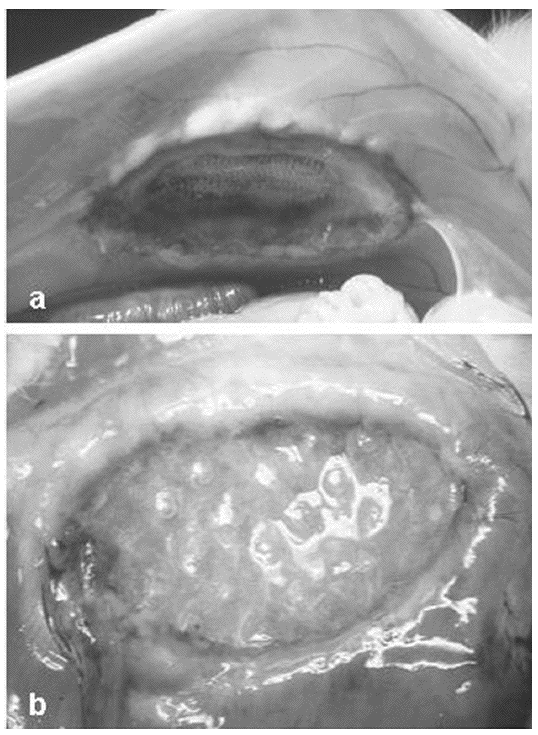

Fig. 2. a) Ausencia de adherencias en los implantes de PL-PU99 a los 14 días postimplante; b) adherencias de tipo laxo en las zonas de sutura del SIS al tejido receptor.

No hubo mortalidad en los animales intervenidos. Las prótesis fueron siempre bien toleradas y no se detectaron signos de infección y/o rechazo de los implantes. No hubo presencia de exudados, manteniéndose la impermeabilidad en el implante. La formación adherencial fue mínima entre la prótesis compuesta y las asas intestinales. Sólo en algún caso, y principalmente en las zonas de anclaje de SIS, se formaron adherencias puntuales, de consistencia laxa (fig. 2). El porcentaje de adherencias en cada uno de los grupos fue estadísticamente significativo (p < 0,05): 0,31 ± 0,03% (PL-PU99) y 31,60 ± 7,35% (SIS).